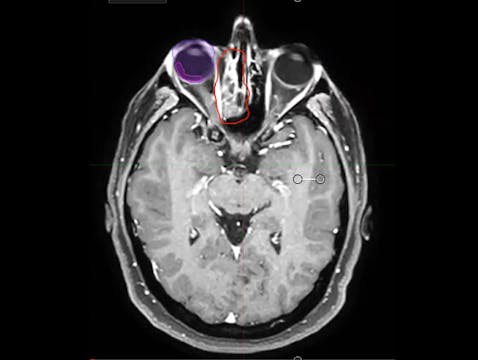

03/15/2022 - Dr. Kenneth Hu - Radiation Oncology - Head and Neck

Chartrounds US - Head and Neck Cancer